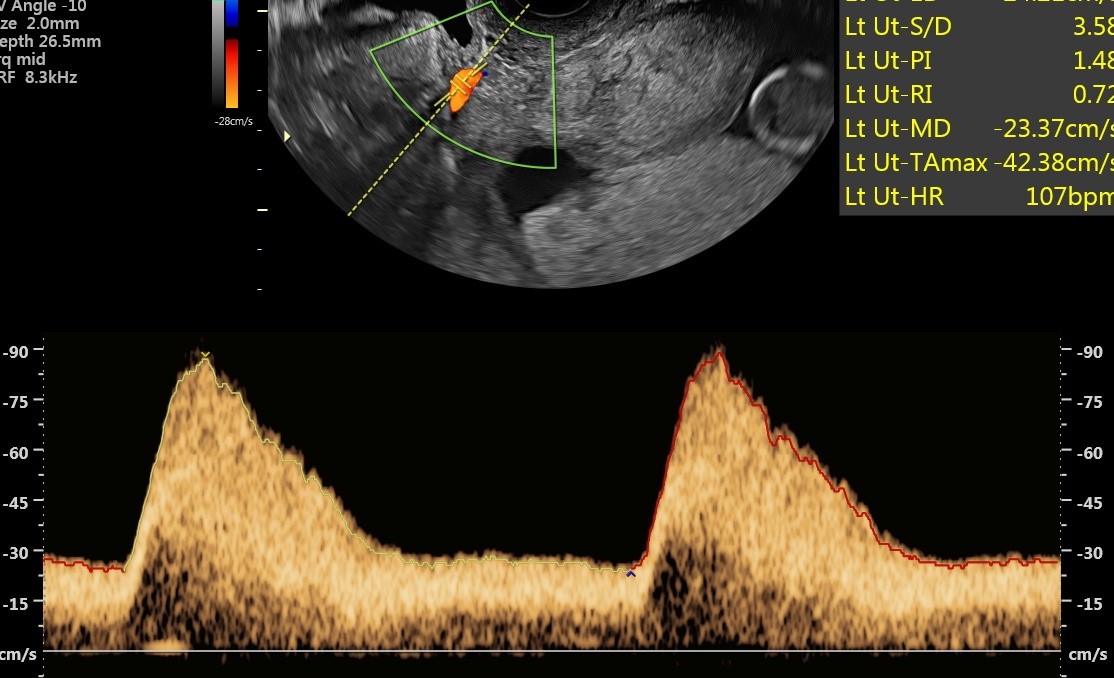

Prawidłowe przepływy w tętnicy macicznej w czasie ciąży, fot. USK-2

Kobietom objętym programem PRENATALPROJEKT wykonywane jest w 1. trymestrze badanie USG, mierzone jest ciśnienie oraz badane są trzy substancje, które pozwalają zdiagnozować funkcjonowanie łożyska i wykryć ww. patologie. Standardowe badania prenatalne obejmują badanie dwóch substancji i nie dają one wystarczająco miarodajnych i pewnych wyników co do prawidłowości funkcjonowania łożyska. W 2. trymestrze ciąży wykonywane jest już samo USG oraz badane ciśnienie. W przypadku wykrycia nieprawidłowości ciężarna zostaje objęta szczególną opieką i monitoringiem. W specjalnie utworzonej aplikacji, którą może pobrać na telefon i z której korzysta także jej ginekolog położnik, podaje mierzone kilka razy dziennie ciśnienie oraz wagę. Lekarz badań prenatalnych, biorący udział w programie decyduje o podjęciu leczenia. W przypadku niewydolności łożyska jest nim podanie odpowiedniej dawki aspiryny. Kobieta przyjmuje ją pod kontrolą lekarza do 36. tygodnia ciąży, który określany jest jako bezpieczny dla rozwoju dziecka, a rozwiązanie ciąży nie stanowi dla niego już takiego ryzyka.